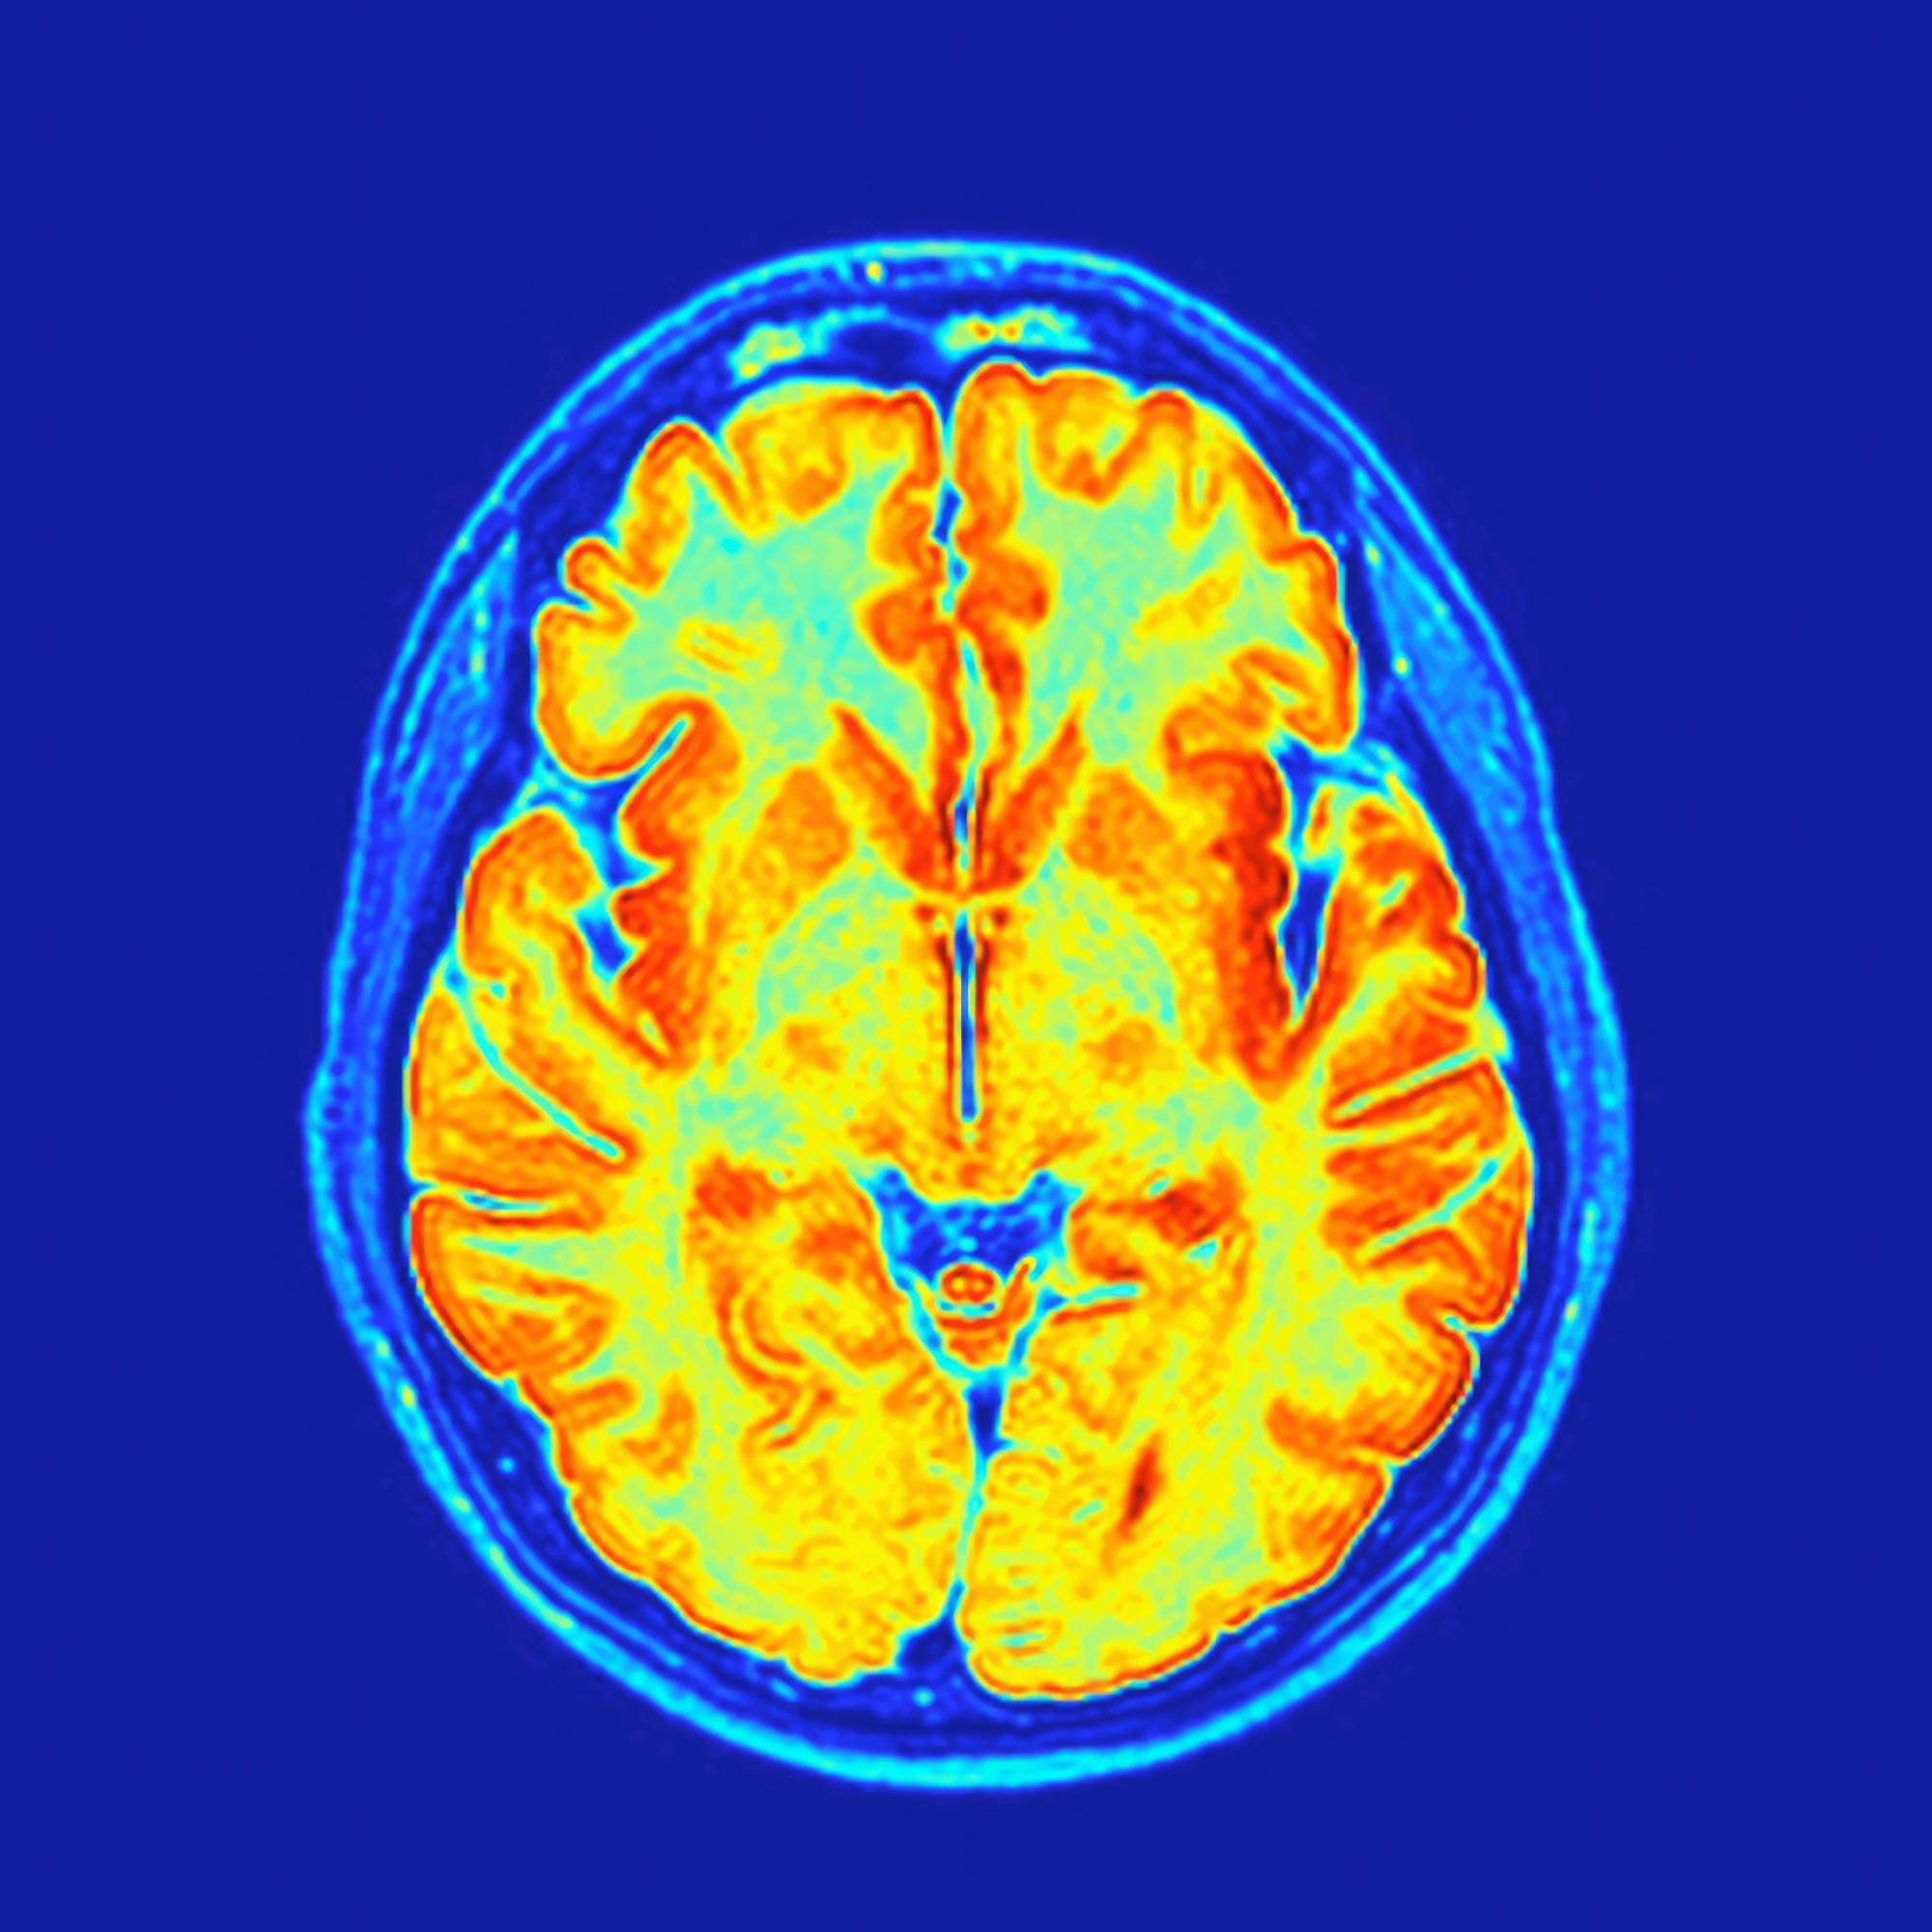

Axial MRI section of a human brain post-processed with colors showing the gray matter, white matter, ventricles and calvariaStudy: Vicarious body maps bridge vision and touch in the human brain. Image credit: FocalFinder/Shutterstock.com